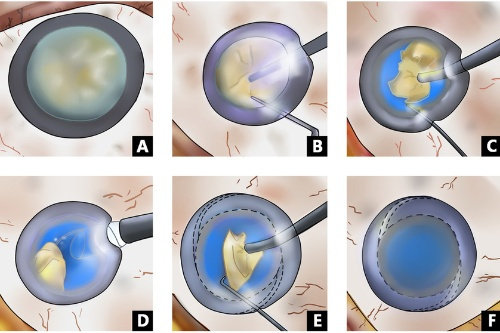

实例一:65岁男性患者,因"右眼视力突然下降伴视物变形"就诊。经检查确诊为右眼黄斑裂孔,视力仅0.1。雷医生为其进行了小创口玻璃体切割联合内界膜剥除手术,术后3个月复查,黄斑裂孔闭合,视力修复至0.6。

实例三:28岁男性,因"右眼外伤后视力丧失"急诊入院。检查发现右眼复杂性视网膜脱离伴玻璃体积血。雷医生急诊为其进行了玻璃体切割联合视网膜复位手术,术后3个月复查,视网膜复位良好,视力修复至0.4。

小创口玻璃体切割术:使用25G/27G超小创口系统,创伤小、修复快

复杂性视网膜脱离复位术:成功概率高,术后视力修复良好

黄斑手术:包括黄斑前膜剥除、黄斑裂孔修复等

根据临床统计,雷医生主刀的视网膜脱离手术成功概率超过90%,黄斑手术视力改善率超过80%。

对于糖尿病视网膜病变患者,通过系统治疗可使90%以上患者避免失明。

手术并发症发生率低于行业平均水平,体现了其优质的手术技巧和丰富的临床经验。

术后随访数据显示,接受雷医生手术治疗的患者满意度高,大部分患者视力得到有效改善或稳定。